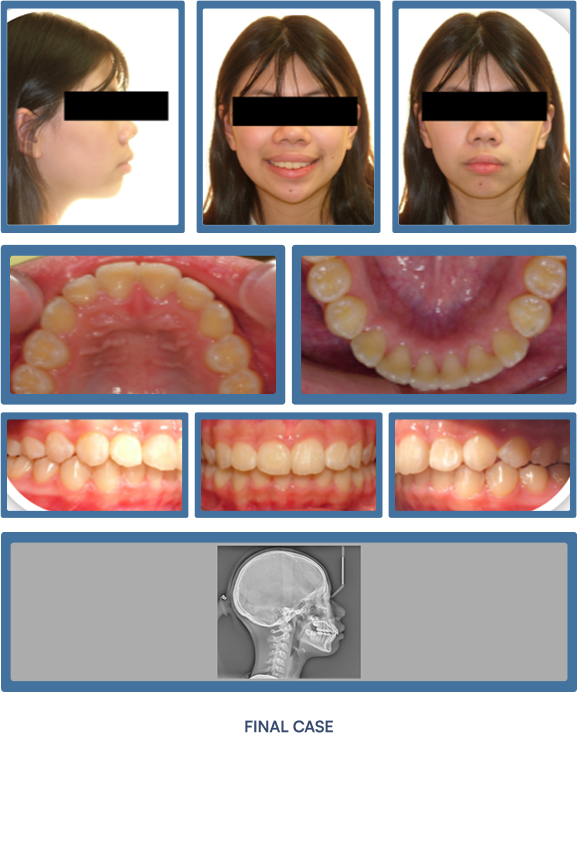

Orthodontic treatment does more than align teeth—it strategically improves the structural support of the lips and lower face. As teeth and jaws are brought into optimal alignment with braces or Invisalign®, many patients experience visibly fuller, more defined lips and an enhanced facial profile. These subtle yet impactful changes contribute to a more youthful, harmonious appearance—making orthodontics a powerful tool not only for oral health, but for facial aesthetics.